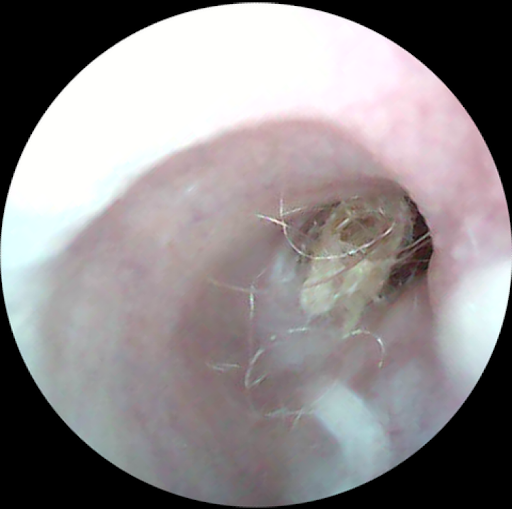

耳の病気、例えば外耳炎、 今までも治療はしてきました。 耳の中を覗いてみて・・・。 「耳の中が赤いくなっていますね」 「けっこう汚れが付着しています」 「腫れています」 言葉で伝えます。 でも、 百聞は一見に如かず。 実際に、 見てもらった方が 今の状態を実感してもらいやすい。 簡単な、 耳の中を見ることのできるカメラを買ってみました。 上の写真、 耳の奥に毛と耳垢が絡まったものが、 見えるでしょ。